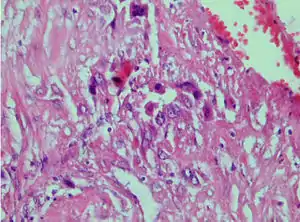

| Photomicrograph showing proliferating intermediate trophoblast with scarce cytotophoblastic and syncytiotrophoblastic elements | |

Placental site trophoblastic tumor is a monophasic neoplasm of the implantation site intermediate trophoblast, and usually a benign lesion, which comprises less than 2% of all gestational trophoblastic proliferations. Preceding conditions include molar pregnancy (5%). Compared to choriocarcinoma or invasive mole, hemorrhage is less conspicuous and serum β-HCG level is low, making early diagnosis difficult.

Immunohistochemistry: Often stains with hPL, keratin, Mel-CAM, EGFR.